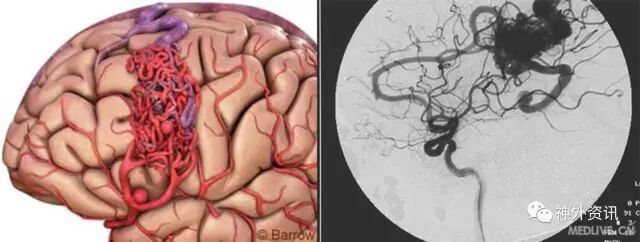

儿童脑血管病

1.儿童脑血管疾病主要包括动静脉畸形(AVMs)、海绵状血管瘤、烟雾病和动脉瘤

2.其他少见的有毛细血管扩张症、静脉瘤、大脑大静脉畸形、硬膜AVM和颈动脉-海绵窦瘘